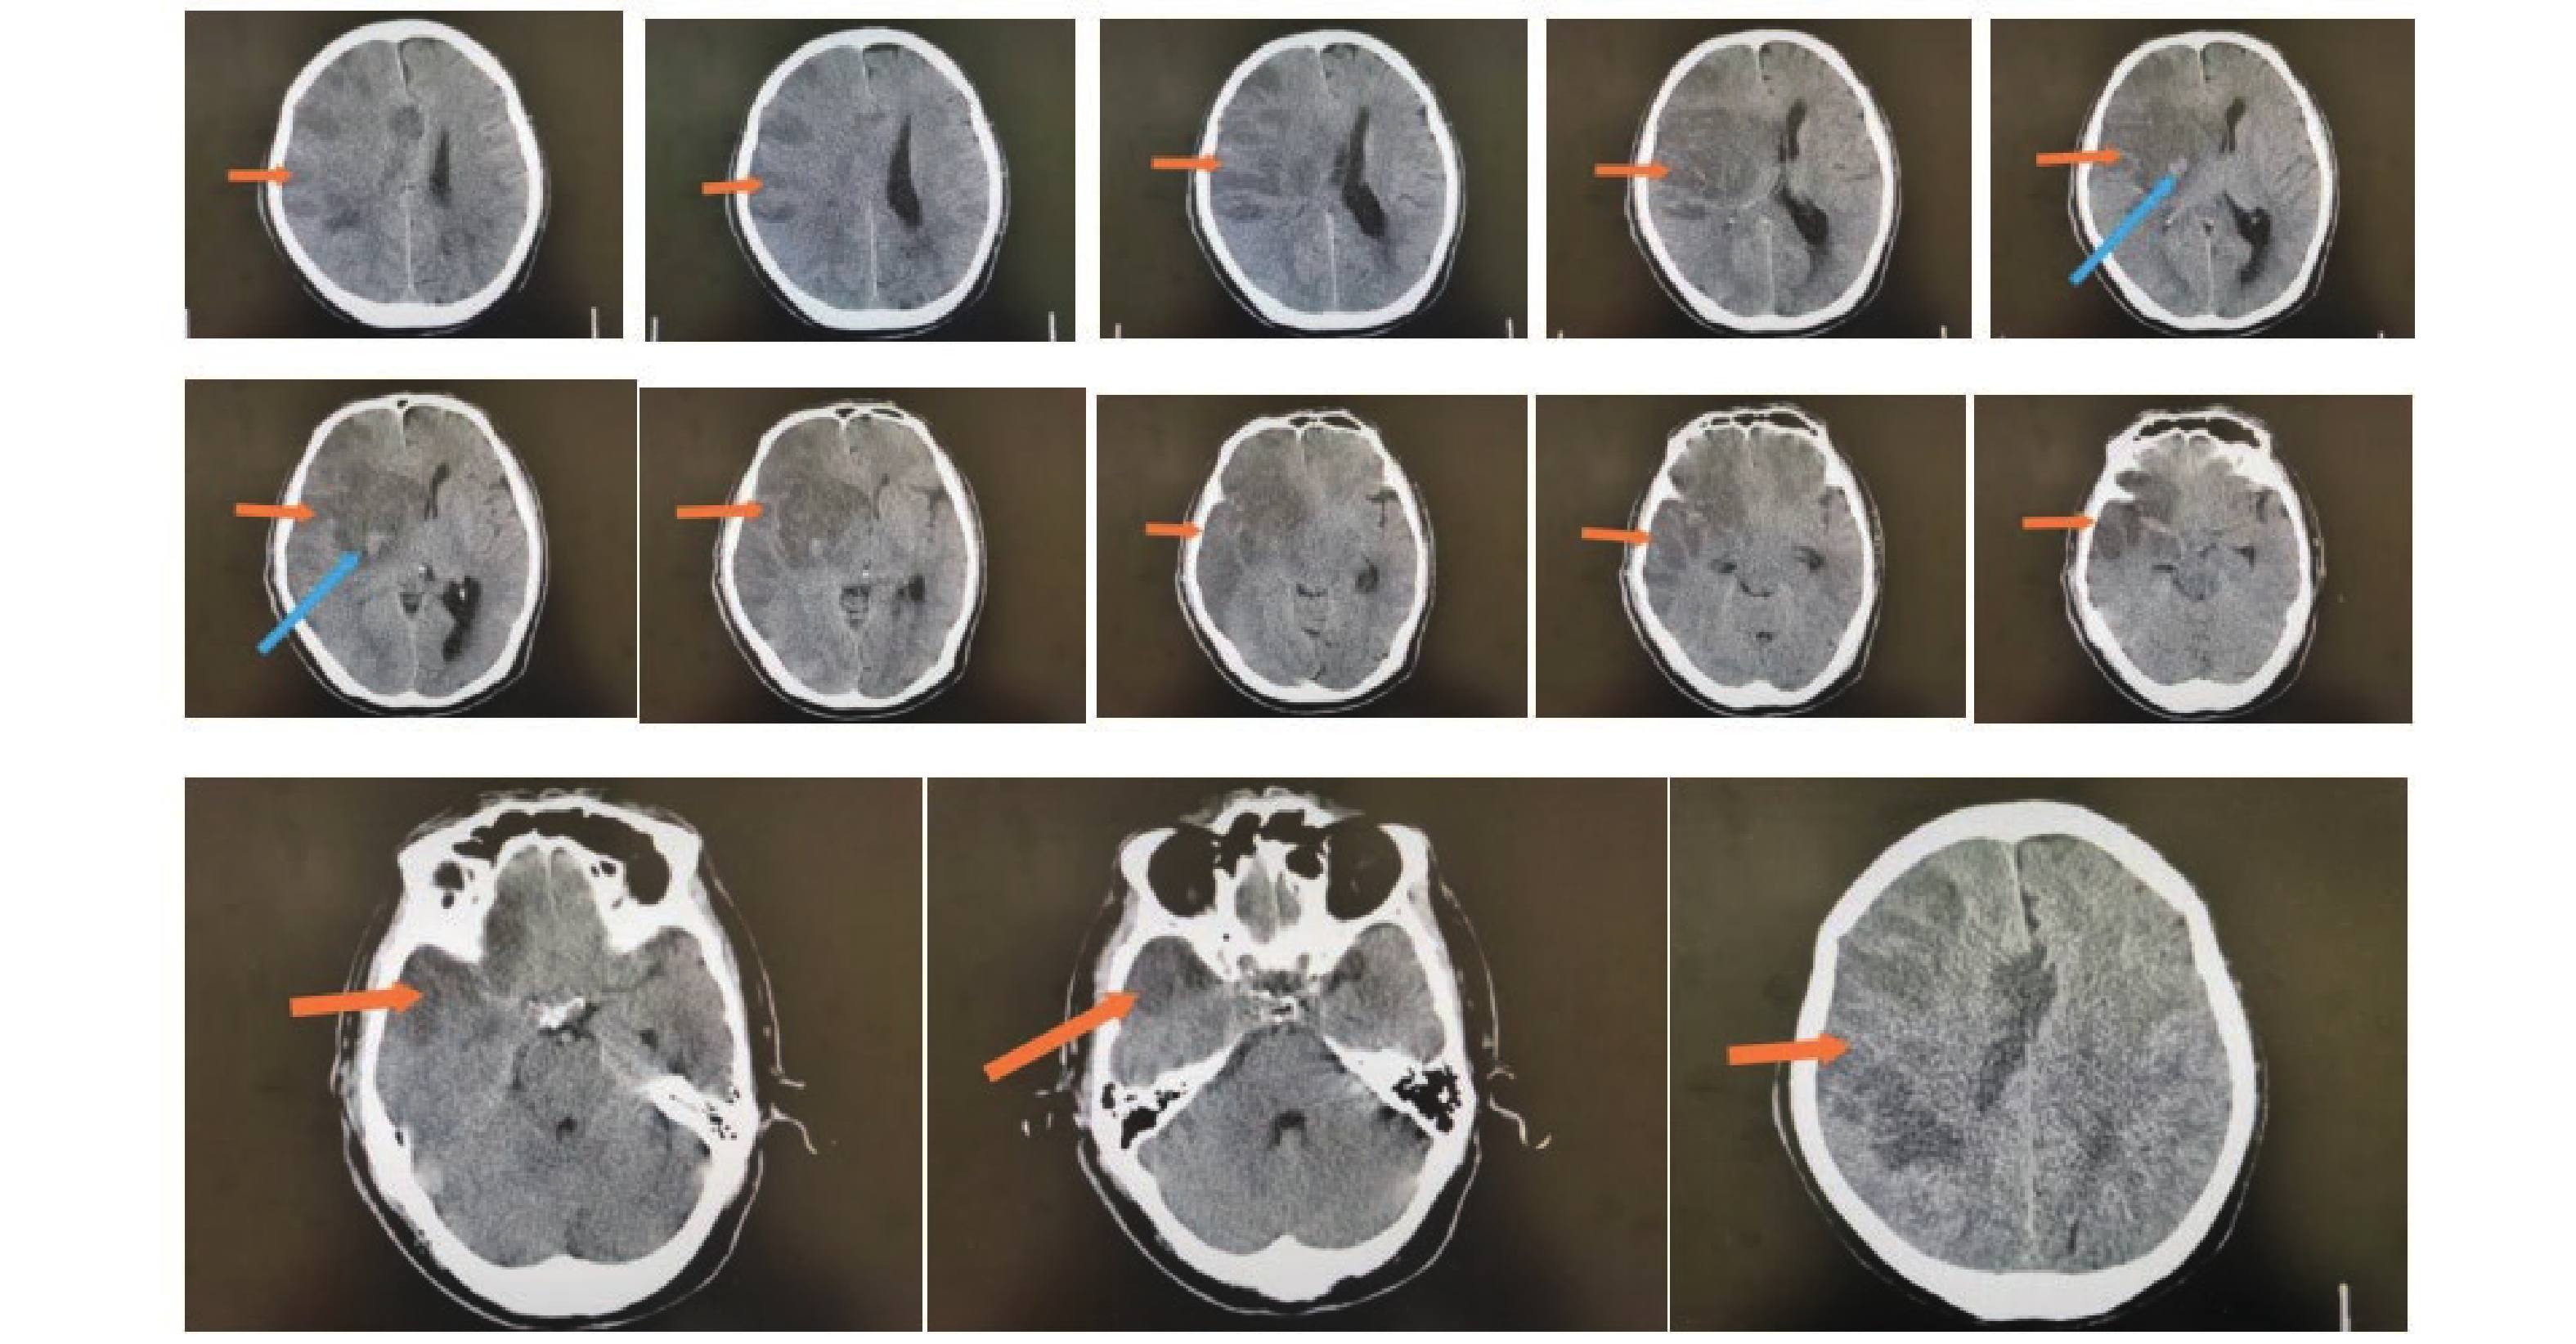

图  2  良好组术前头颅影像学表现

注:男性患者,75岁,从CT上看右侧额叶、颞叶、顶叶、岛叶大面积脑梗塞伴出血,中线左移。其中橙色箭头指向低密度区为梗塞区,蓝色箭头指向较高密度区为出血。

Figure  2.  Preoperative cranial imaging findings in the good outcome group